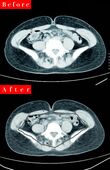

内臓脂肪を減らしてマイナス6kg!

[写真 2/10枚目] 内臓脂肪を減らしてマイナス6kg!